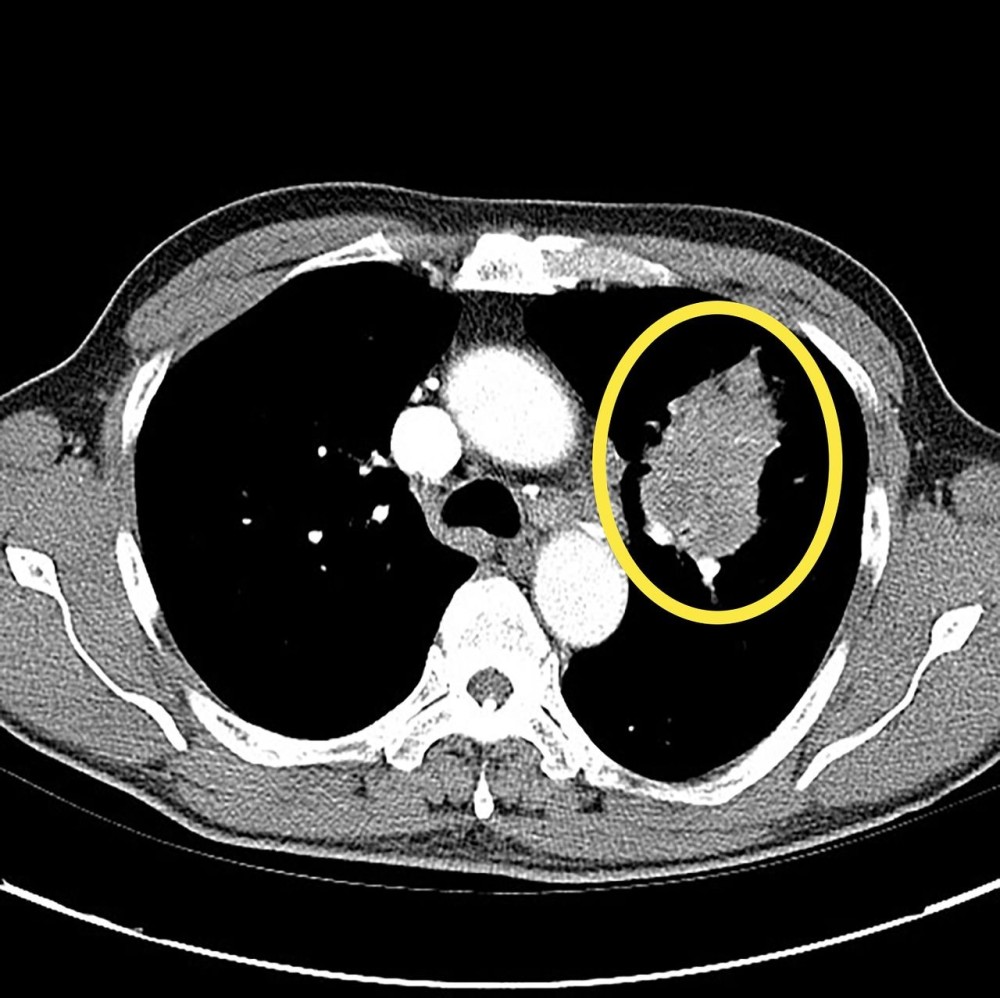

폐암 환자의 엑스레이 검사 사진

폐암 환자의 CT 검사 사진